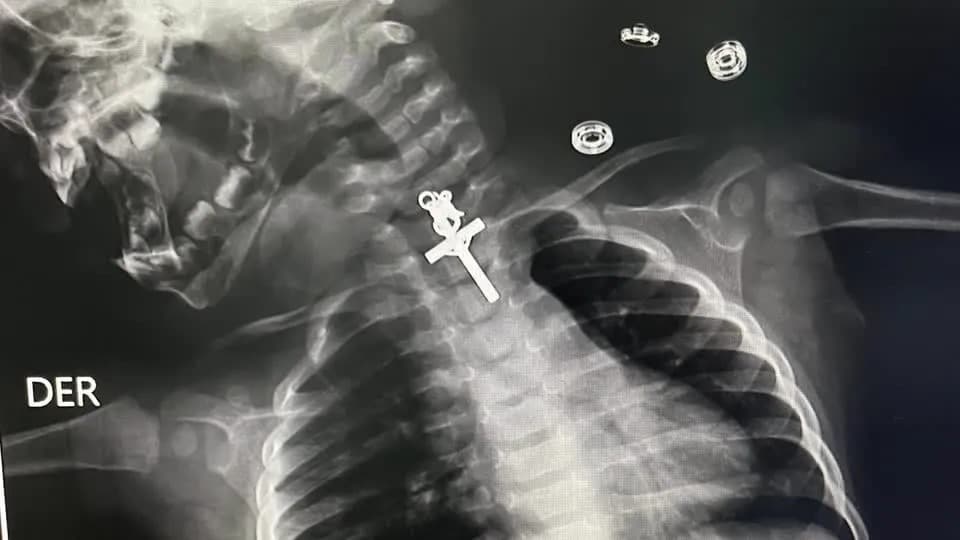

Um bebê de 10 meses foi submetido a uma cirurgia de retirada de um crucifixo do esôfago, no último sábado (11/11), no Hospital Victor Lazarte Echegaray, em La Libertad, no Peru.

A equipe médica local, que atendeu a criança, retirou o ‘corpo estranho’ com o procedimento de endoscopia, após as imagens do Raio-x detectarem o crucifico alojado no no terço superior do esôfago.

“O procedimento foi muito complicado porque era um crucifixo e estava alojado no terço superior do esôfago. Mesmo quando tentamos retirá-lo inicialmente, não conseguimos, estava preso, então tentamos várias vezes até que consegui retirar o corpo estranho”, disse o médico responsável, Luis Esteves Cabanillas.